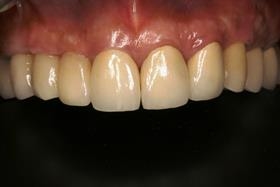

治療後

病患恢復自信笑容。